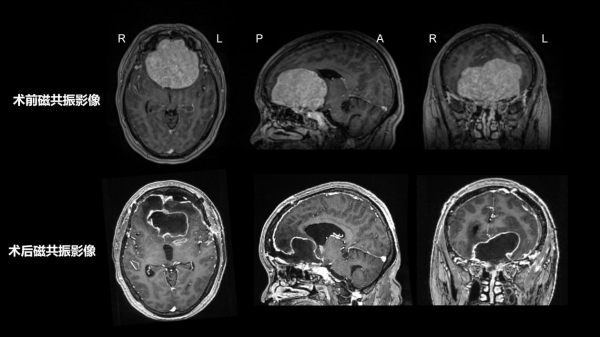

入院后,MRI和CT检查进一步揭示了病情的复杂性:前颅底肿瘤体积达7.4cm×7.3cm×7cm,额叶、下丘脑、穹隆、三脑室及双侧脑室严重受压,肿瘤甚至向筛窦、鼻腔内生长;左额部还有一枚1.9cm×1.5cm×1.3cm的肿瘤。CT显示前颅底骨质已被破坏,双侧大脑前动脉被肿瘤包绕,双侧颈内动脉及大脑中动脉也受压移位。

面对病变巨大、位置深在、紧邻重要神经和血管、术后脑脊液漏风险高等多重挑战,李学军教授团队没有丝毫懈怠。科室组织了术前病例讨论,决定一期手术切除多发脑膜瘤,同时行颅底重建。针对术中可能出现的出血、感染、神经损伤等风险,团队制定了详尽的应急预案,从术前评估到术后监护,每一个环节都做到心中有数、手中有策,为手术安全筑牢了坚实保障。

两小时的显微镜下精细操作,不仅彻底清除了病灶,更最大程度减少了对正常脑组织的牵拉与损伤,从根源上降低了复发风险。同时,团队还为她完成了细致完美的颅底修复重建,为后续康复打下坚实基础。